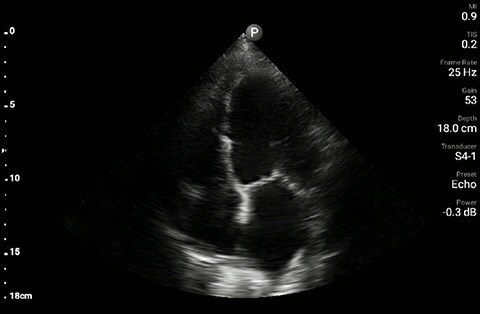

In this Lumify case study and summary video, Dr. Sara Nikravan discusses how she used her Philips Lumify handheld ultrasound system to guide the diagnosis and treatment of a patient experiencing shortness of breath.

Determining the cause of respiratory distress in the acutely ill can be challenging. POCUS with a three-point exam (F-TTE, IVC collapsibility, and lung ultrasound), as performed above, has been endorsed in this patient population as it can increase diagnostic accuracy in a timely fashion, especially as it pertains to acute decompensated heart failure.4 Furthermore, the use of a small portable device allows for convenience with rapid setup and use while minimizing the uptake of space. This becomes especially important when caring for patients that often have many providers attempting to provide care and initiate interventions at the same time, given the acute nature of their illness and potential for further rapid de-compensation.